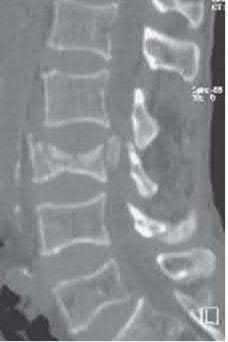

A 45-year-old male is involved in a high-speed motor vehicle collision and presents with the cervical spine radiograph findings typical of traumatic spondylolisthesis of the axis.

Which of the following describes the primary mechanism of injury for this specific fracture pattern (Hangman's fracture)?

Explanation

A 'Hangman's fracture' is a traumatic spondylolisthesis of the axis (C2) involving fractures through the pars interarticularis. The classical mechanism of injury in modern trauma (e.g., unrestrained passenger hitting the windshield) is hyperextension and axial loading. Flexion-distraction typically causes Chance fractures, while flexion-compression typically causes anterior wedge or teardrop fractures.